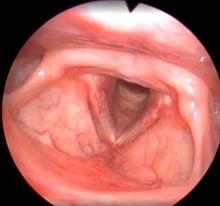

Рис 2А. Двусторонний паралич гортани. До операции.

Рис 2В Двусторонний паралич гортани. 1 месяц после операции